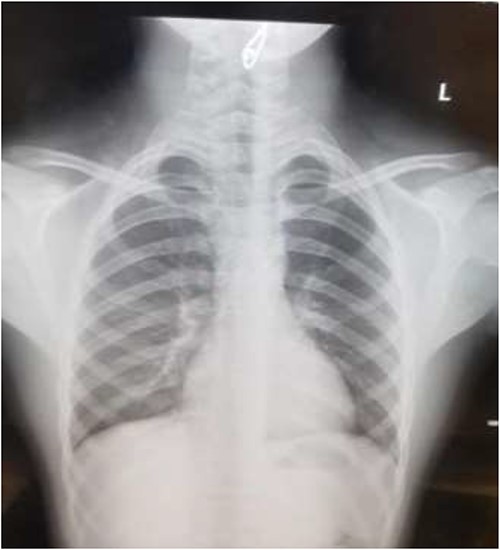

The first case is of a 7-year-old child presenting with a history of barbed wire inhalation. X-ray imaging of his neck and chest showed a radio-opaque object visible in the upper airway with sharp edges (Figs 1 and 2). Due to the position of the foreign body, endotracheal intubation was not feasible. A trial of apnoeic oxygenation using high-flow nasal oxygenation was used as an alternative, and this allowed for an unobstructed view of the larynx, facilitating the safe removal of the foreign body (Fig. 3).

AP chest radiograph showing the sharp-edged radio-opaque object.